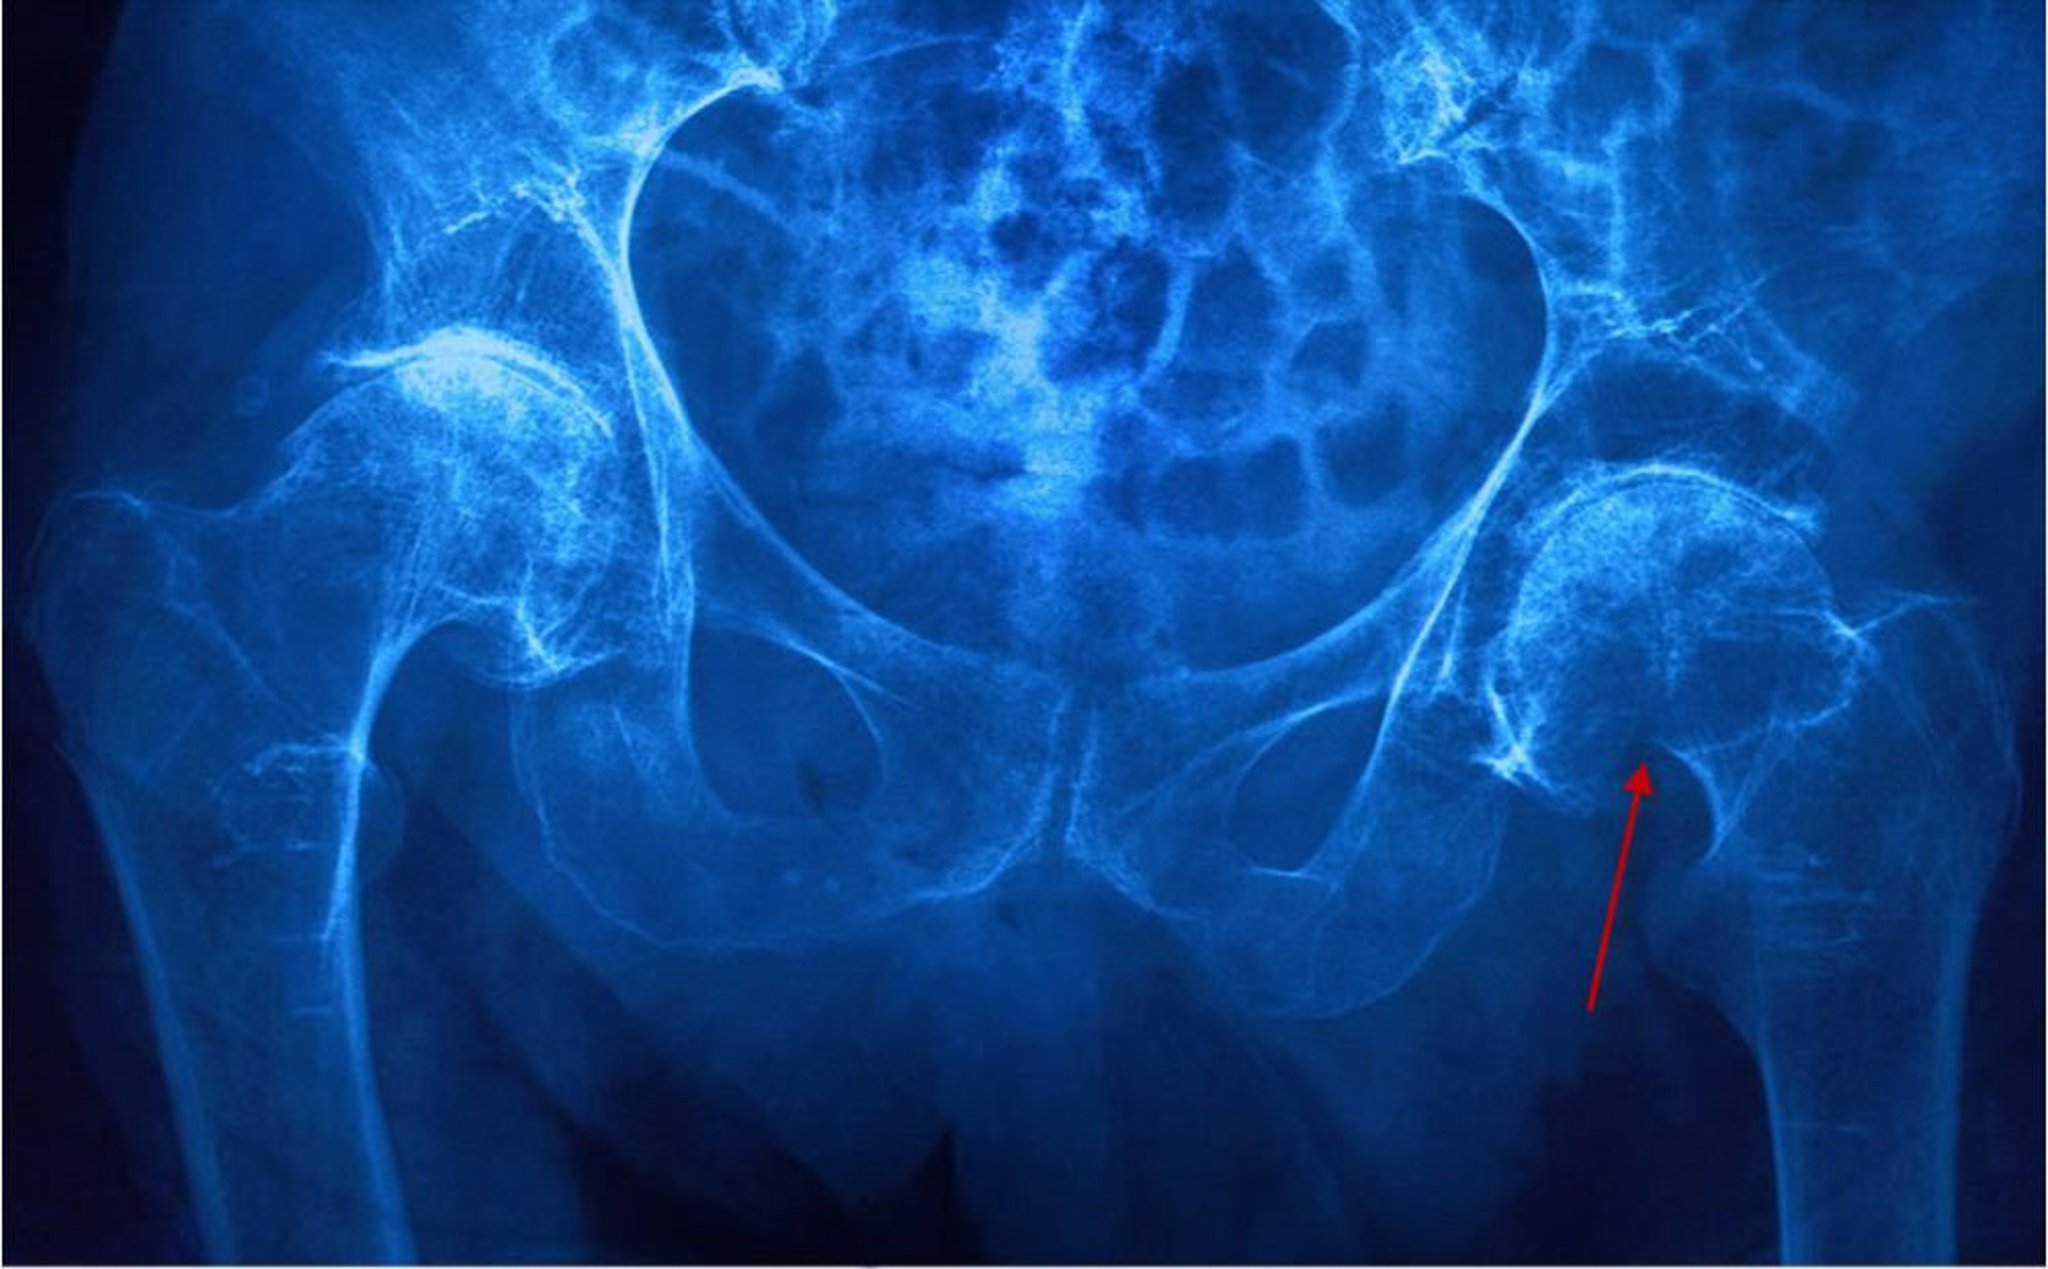

Перелом шийки стегнової кістки

На даній рентгенограмі показаний перелом шийки лівої стегнової кістки (субкапітальний), про що свідчить укорочення шийки стегнової кістки та руйнування окістя (стрілка).